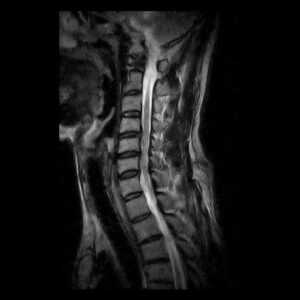

2. 画像検査

MRI:神経の圧迫や椎間板の状態を詳細に評価でき、ヘルニアや脊髄圧迫の有無を確認します。神経の圧迫などには最も優れた検査がMRIであり、詳しく調べるときは重要な検査となります。